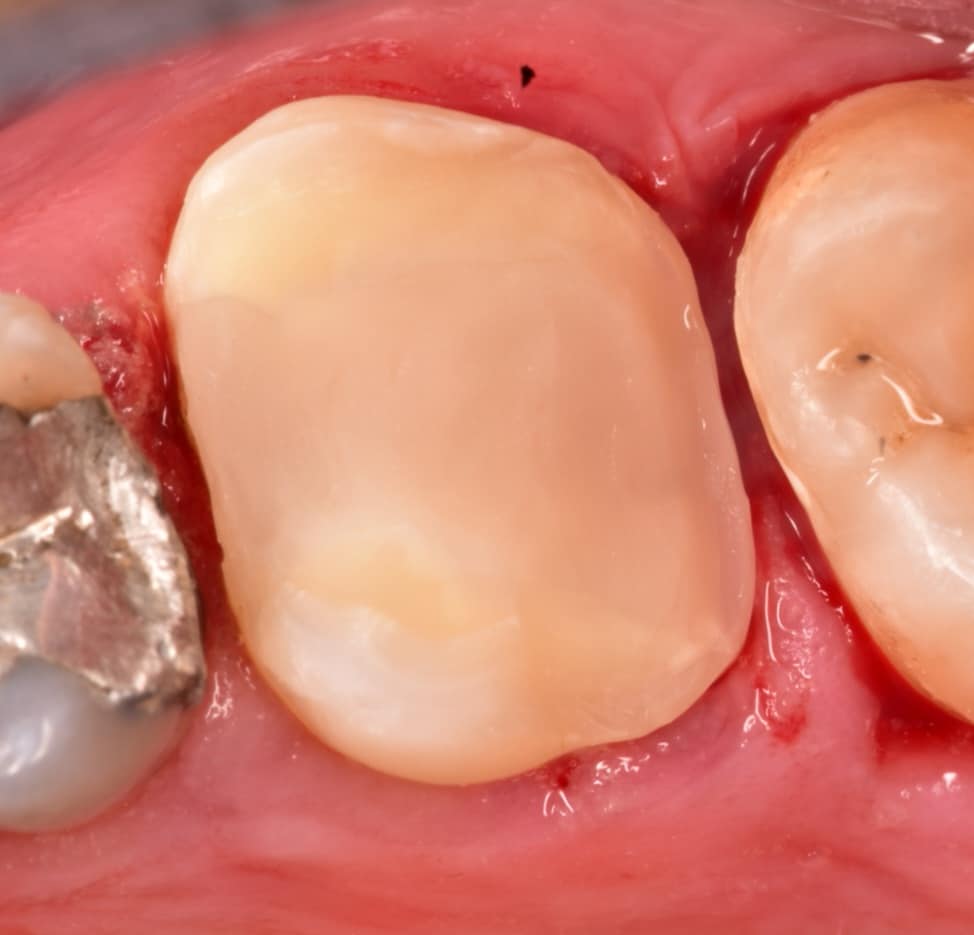

After rubber dam removal

Final result,